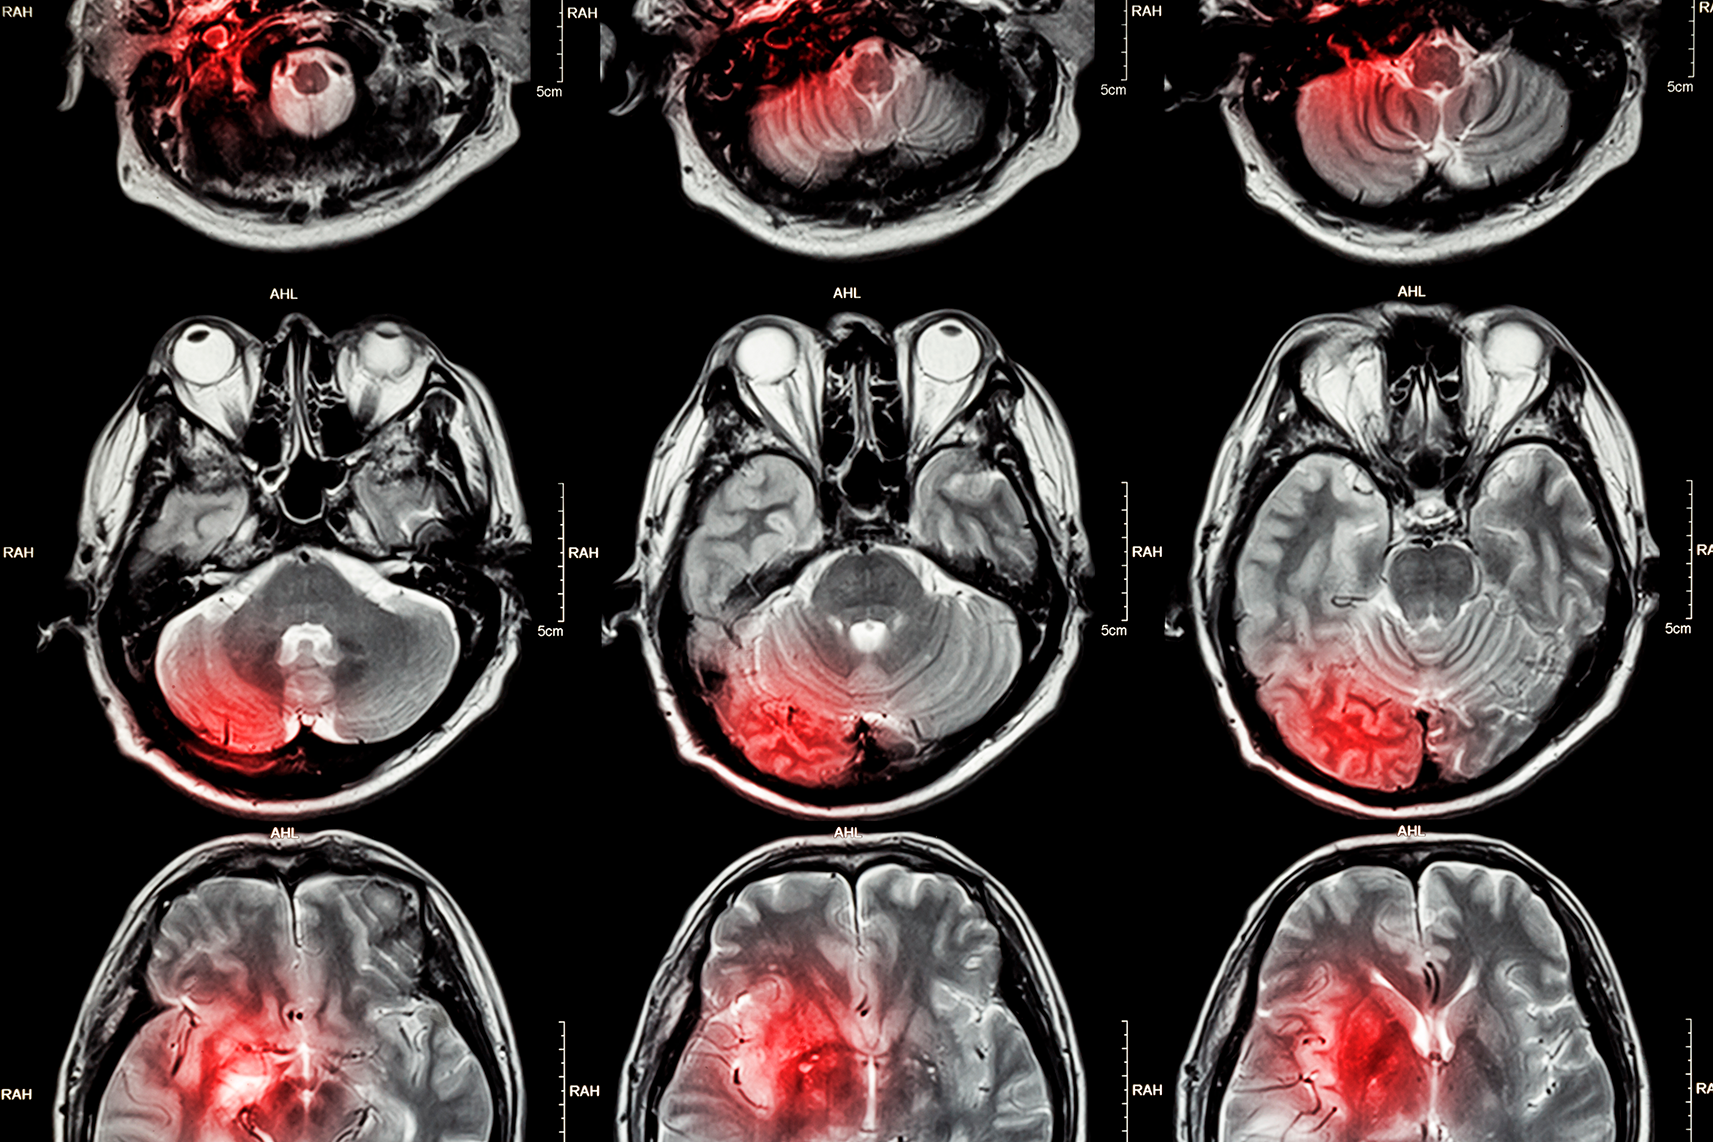

Hemorragia cerebral

La hemorragia cerebral es una condición potencialmente mortal en la que se produce un sangrado en el interior del cerebro. Esto puede ocurrir como resultado de una lesión, una enfermedad congénita o una enfermedad vascular.

¿Cuáles son los síntomas? Los síntomas de la hemorragia cerebral incluyen dolor de cabeza grave, vómitos, confusión, pérdida de la consciencia, parálisis, convulsiones y cambios en el comportamiento. Si se detecta a tiempo, algunos de los síntomas pueden ser tratados con éxito.

¿Cuál es el tratamiento? El tratamiento más común es una cirugía para detener el sangrado y reducir la presión en el cerebro. También se pueden administrar medicamentos como anticonvulsivos y diuréticos para controlar los síntomas. La rehabilitación puede ayudar a los pacientes a recuperar la función cerebral.

Derrame cerebral

Un derrame cerebral ocurre cuando hay una interrupción del flujo sanguíneo en el cerebro. Esto puede ser causado por una ruptura de un vaso sanguíneo o un bloqueo de un vaso sanguíneo. Esta interrupción del flujo sanguíneo impide que las células del cerebro reciban el oxígeno y los nutrientes que necesitan para funcionar correctamente.

Esto puede causar una variedad de síntomas, desde pérdida de la memoria a parálisis parcial. Si no se trata, un derrame cerebral puede tener consecuencias a largo plazo, como discapacidad, e incluso poner en riesgo la vida. Por lo tanto, es importante reconocer los signos de un derrame cerebral y buscar atención médica inmediata.

Aneurisma cerebral

Un aneurisma cerebral es la dilatación anormal de una arteria o una vena en la región del cerebro. Esta dilatación se produce cuando la pared de la arteria se debilita y se forma una bolsa con forma de globo. La mayoría de los aneurismas cerebrales se encuentran en las arterias que llevan la sangre desde el corazón al cerebro. Esta afección es una de las principales causas de hemorragia intracraneal y puede ser fatal.

¿Cuáles son los síntomas? Los síntomas más comunes son dolor de cabeza intenso, visión borrosa, pérdida de la conciencia, fatiga, náuseas, vómitos y convulsiones.

¿Cuál es el tratamiento? El tratamiento depende de la ubicación y el tamaño del aneurisma, así como de otros factores. Los tratamientos incluyen cirugía, terapia con láser, embolización y medicamentos.